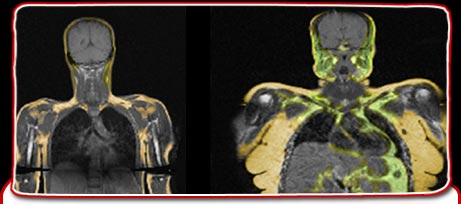

In fact, the larger you are the higher your metabolic rate, the amount of energy your body uses at complete rest, will be. This is because when your body is at complete rest larger people need more energy to pump the blood around the body and to keep moving. Just as a big car uses more fuel so a bigger person uses more energy.